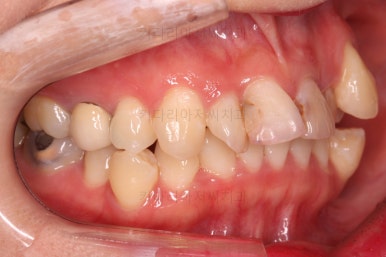

초진 시 입안의 모습입니다.

이미 썩어서 부러진 치아도 몇 개 보이고요.

많이 삐뚤어진 치아쪽은 양치가 힘들어 이미 많이 썩어 있는 상태에 덧니쪽은 잇몸도 많이 내려간 상태였습니다.

말그대로 교정치료 뿐만 아니라 전반적인 치료가 필요한 상황이었습니다.